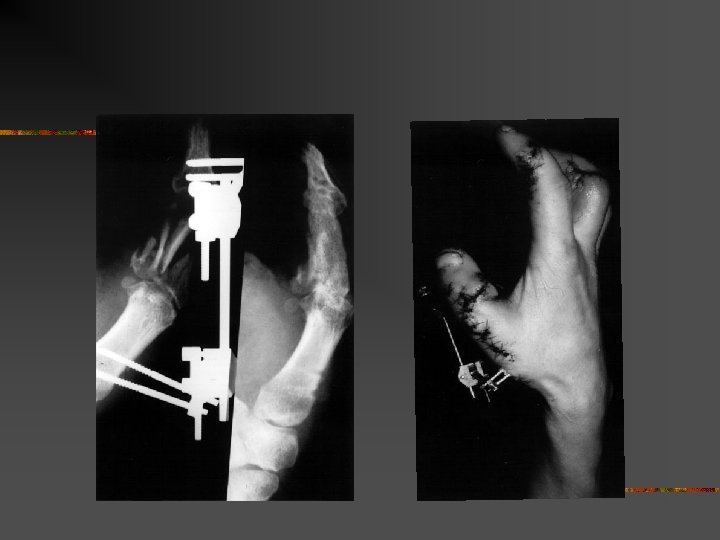

Traumatisme par blast n n Onde de choc forte Blast solide : lésions vasculaires nerveuses et osseuses Blast aérien : lésions viscérales Lésions complexes pluritissulaires

Matériel et méthodes n n n Etude rétrospective de 24 dossiers Entre 1976 ET 2002 Age moyen : 25, 6 ans (13 à 61 ans) 50% < 20 ans Lésions unilatérales : 20 Lésions bilatérales : 4

Résultats n Agents vulnérant : n n n 10 bombes artisanales 5 pétards 3 grenades 3 pétard à taupe 2 dynamites 1 détonateur

Homme 16 ans. Traumatisme des deux mains par bombe artisanale

Homme 16 ans. traumatisme des deux mains par bombe artisanale amputation à gauche et lambeau IOP à droite

Homme de 61 ans. Traumatisme index droit par pétard à taupe. Dévascularisation. Revascularisation par pontage veineux

Au total n n Gravités des lésions Patients jeunes Consolidation moyenne de 28 semaines Sur 24 patients : n n n 1 amputation bilatérale en avant bras 1 amputation de la main 8 mains séquellaires graves : 5 mains sans pouce n 1 pouce sans main n 2 mains figées n

Traitement : n En urgences : n n Entre J 3 et J 5 : n n n Parage Stabilisation des lésions osseuses Revascularisation Parage secondaire Couverture Prévention +++